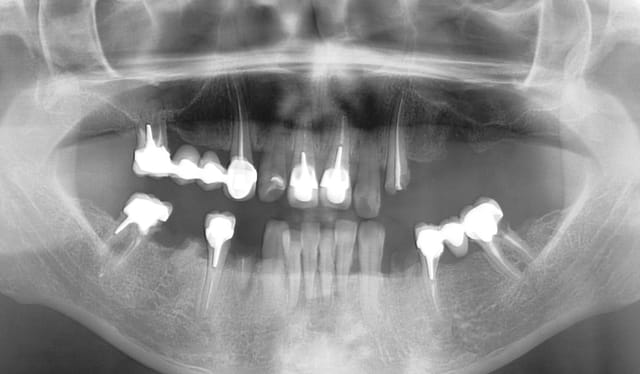

Patiente pas revenue depuis plus de 4 ans et demi.

Je l'ai vu début novembre pour un contrôle, et j'ai pu constaté qu'elle avait bien suivi mes conseils relatifs à l'HBD...

Rien n'a bougé, même les deux stellites sont impeccables!

Cela fait plaisir, le travail bien fait, durable, prévisible, peu importe qu'il s'agisse de biodentine ou d'endo-ic-couronne...

Pano 10022011 ujohsu - Eugenol

Pano 07112015 hvxbbe - Eugenol